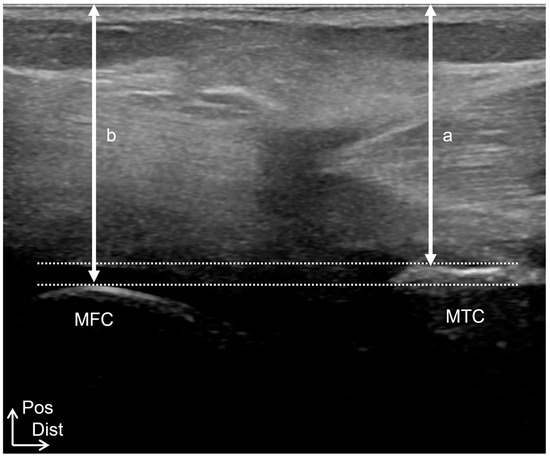

On the other hand, 24 knees were defined as knee OA with a posterior shift of less than 3.8 mm of the medial condyle gap and less than 4.6 mm of the lateral condyle gap; the other 39 knees were defined as knee OA without a posterior shift (Figure 5). The MME of the posteriorly shifted group, in which the tibia was shifted posteriorly compared to the medial and lateral gaps of the Control group, was significantly greater than that of the non-posteriorly shifted group (Table 5). In addition, the posteriorly shifted group showed a significantly lower knee extension angle and significantly greater joint effusion than the non-posteriorly shifted group.

Figure 5.

Knee OA with posterior shifted. A long-axis image was obtained to visualize the most prominent posterior points of the medial femoral condyle and the most prominent posterior point of the medial tibial condyles. a = 23.2 mm. b = 24.9 mm. Medial condyle gap (a − b) = −1.7 mm. MTC, medial tibial condyle; LFC, lateral femoral condyle; Pos, posterior; Dist, distal.